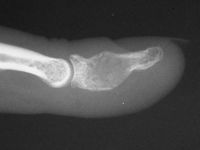

| A corticocancellous strut bone graft was placed in the defect to stabilize the weakened bone. |

| Late result. |